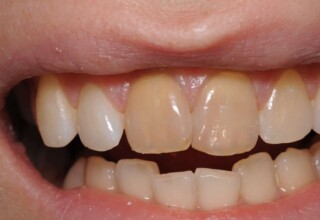

Αποκατάσταση διαστημάτων μεταξύ κεντρικών και πλαγίων τομέων

Τα διαστήματα έχουν δημιουργηθεί κυρίως λόγω των στενών πλαγίων. Μετά την ολοκλήρωση της ορθοδοντικής θεραπείας τα διαστήματα “έκλεισαν” με την τοποθέτηση δύο αποκαταστάσεων σύνθετης ρητίνης.